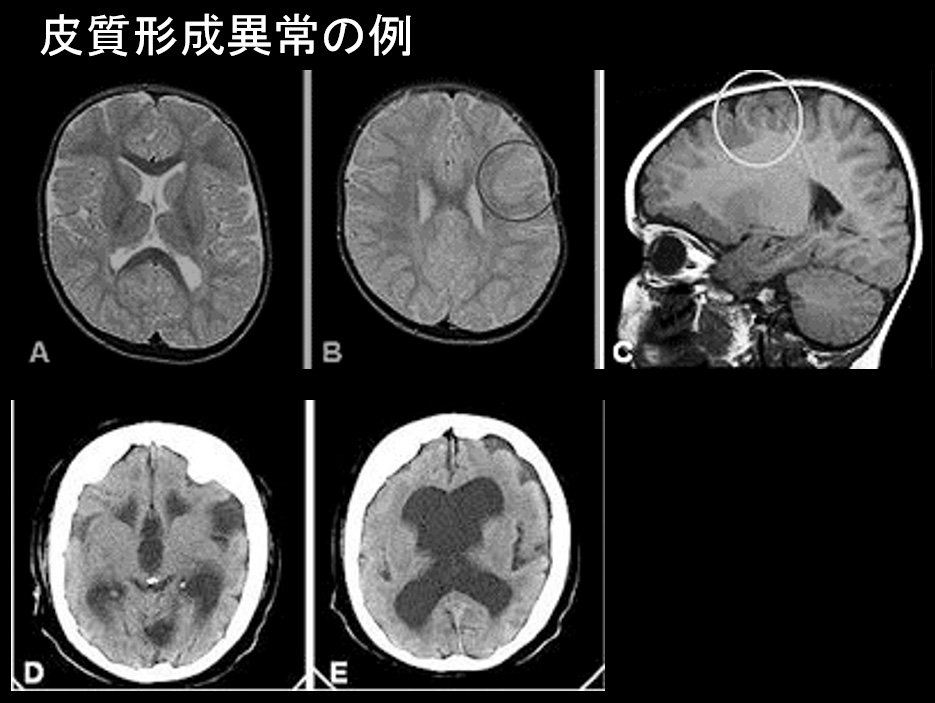

皮質形成異常の例

琉球大学 UR-DBMS より

Cerebral imaging in patient 1 (A–C) and patient 2 (D, E). Panels A–C show axial, T2 weighted (A, B) and sagittal, T1 weighted (C) MR images with deficient gyration of the frontal lobes and an area suspected of being cortical dysplasia in patient 1 (circles in panels B and C). Panels D and E show CT images from patient 2, with enlarged ventricles, wide opercular regions, and clear signs of frontal lobe cortical malformation with an abnormal flat cortex with only a few, simple and shallow sulci.

(Willemsen MH et al. Mutations in DYNC1H1 cause severe intellectual disability with neuronal migration defects. J. Med. Genet. 49: 179-183, 2012)